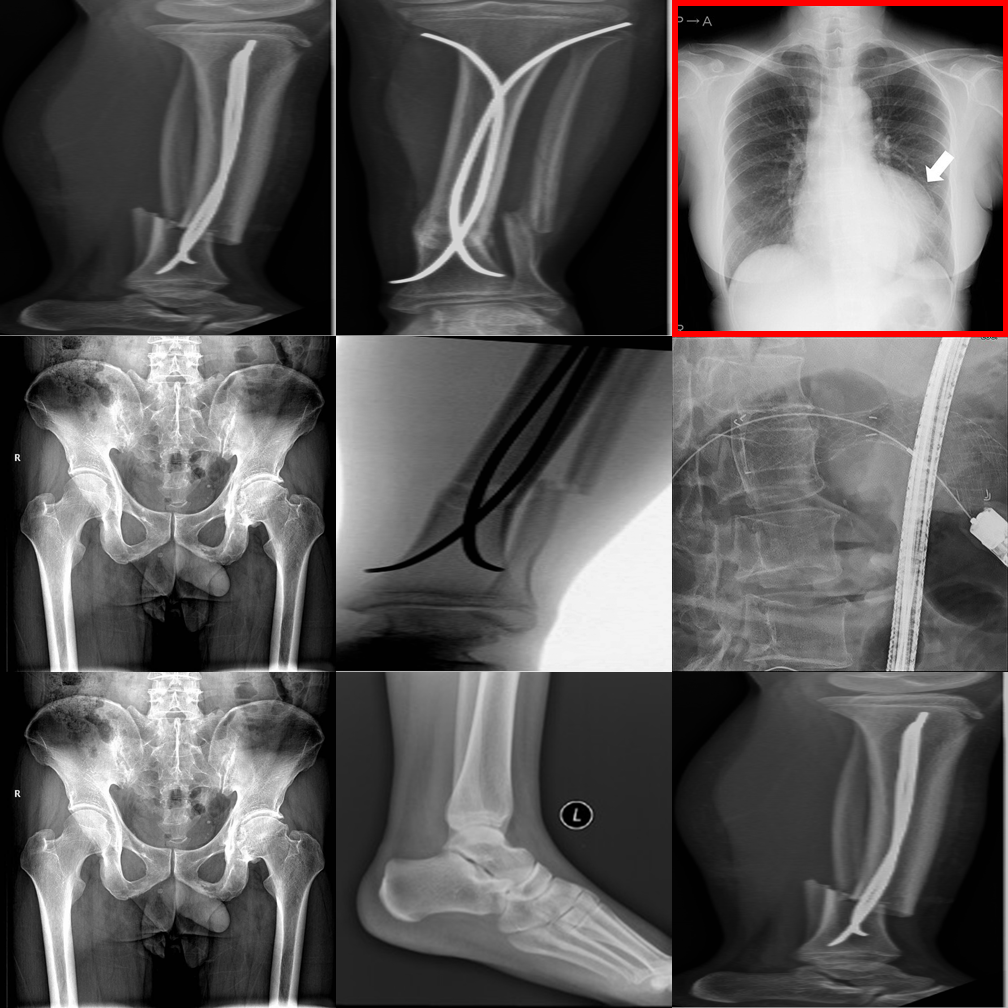

Dense 3×3 grids with 8 distractors. Systematic comparison is essential.

Dense 3×3 grids make it harder to compare even when the outlier is highlighted.

Smaller proprietary models struggle with visual referring on larger grids.

Even the latest reasoning models fail on 3×3 visual referring tasks.

Incorrectly flags a perfectly consistent 3×3 negative control as an outlier.

Hallucinates a detailed physical abnormality despite the uniform grid.

Shows strong "always-find-something" bias triggered by the bounding box.

Fabricates a difference in a perfectly consistent 3×3 grid.

Generates plausible-sounding but entirely fabricated clinical reasoning.

One of few models capable of correctly suppressing false alarms on 3×3 grids.

Proprietary models perform best on visual referring with clear anatomy differences.

Cross-anatomy mismatches are well handled when the panel is directly highlighted.